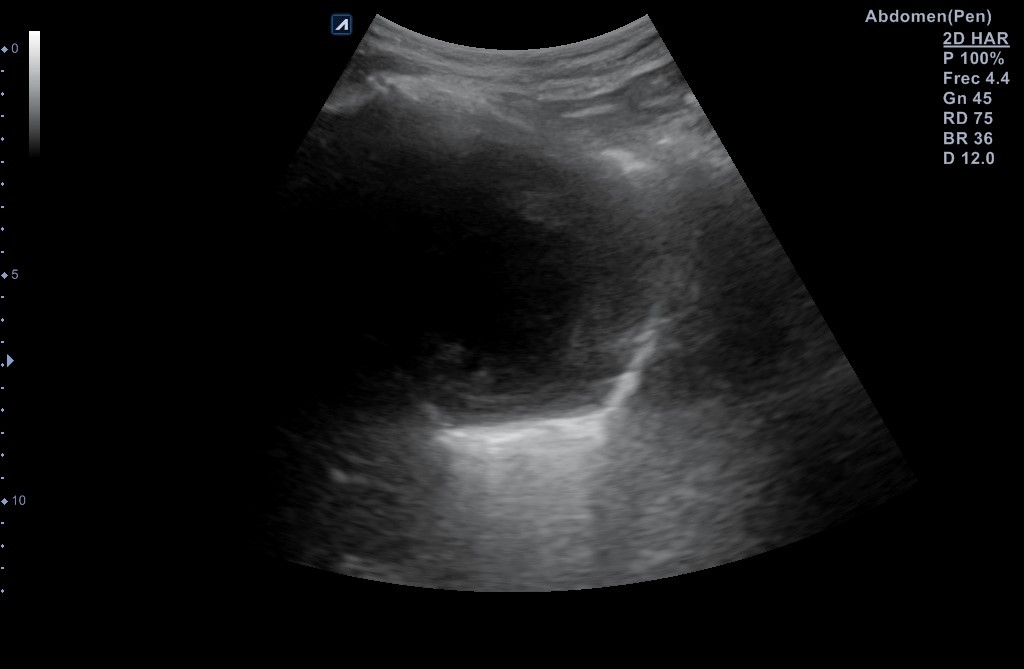

Se realiza ecografía pulmonar donde se identifica una masa anterior en el vértice del pulmón derecho, de aspecto sólido con centro necrótico de unos 7-8 cm de diámetro en anteroposterior y transversal, sin poder precisar diámetro longitudinal por interposición de costillas, clavícula y esternón.